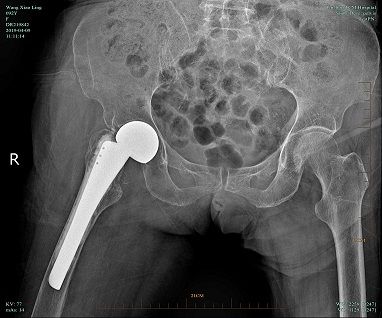

完成手術(shù)準(zhǔn)備后,4月4日由喻燦明副主任中醫(yī)師主刀行“右人工股骨頭置換術(shù)”。(術(shù)后復(fù)查片見圖2)

- 圖 2 -

術(shù)后第二天,王阿婆已能下地行走(具體情況見以下視頻),相信在不斷的功能鍛煉后,阿婆能恢復(fù)一定的生活自理能力。